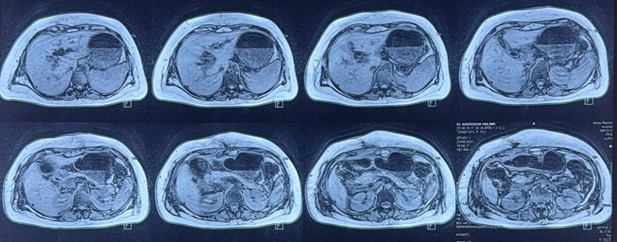

The liver was of normal size and regular contours. Multiple (at least seven) rounded, well-defined nodular lesions were identified in segments V, VII, and VIII, appearing hypointense on T1-weighted images and hyperintense on T2-weighted images, with diffusion restriction and peripheral enhancement after gadolinium administration. The largest lesion was located in segment VII and measured 14 × 11 mm.

The gallbladder was not visualized, either in its anatomical bed or in an ectopic location. The common hepatic duct was dilated to 10 mm, with marked wall thickening and intense enhancement following gadolinium injection. Moderate dilatation of the intrahepatic bile ducts was noted. Aerobilia was present within the common hepatic duct and intrahepatic bile ducts, producing focal signal voids in certain areas. There was no dilatation of the common bile duct or the main pancreatic duct.

The Kehr T-tube was visualized within the common bile duct, extending to the level of the biliary confluence. The distal tips of the Redon drains were identified in the perihepatic region (adjacent to segment VIII) and in the subhepatic space (adjacent to segment III).

The pancreas was enlarged, predominantly at the head (anteroposterior diameter of 35 mm), with loss of normal lobulation and homogeneous enhancement after gadolinium administration, consistent with a reactive appearance (normal serum lipase). Diffuse infiltration of the mesenteric fat was observed both above and below the mesocolon. No significant peripancreatic fluid collection was identified.

A small amount of intraperitoneal fluid was present in the perihepatic and perisplenic regions, as well as within the paracolic gutters.

Figure 3: MRCP showing multiple nodular lesions located in hepatic segments V, VII, and VIII, with absence of gallbladder visualization in the gallbladder fossa.